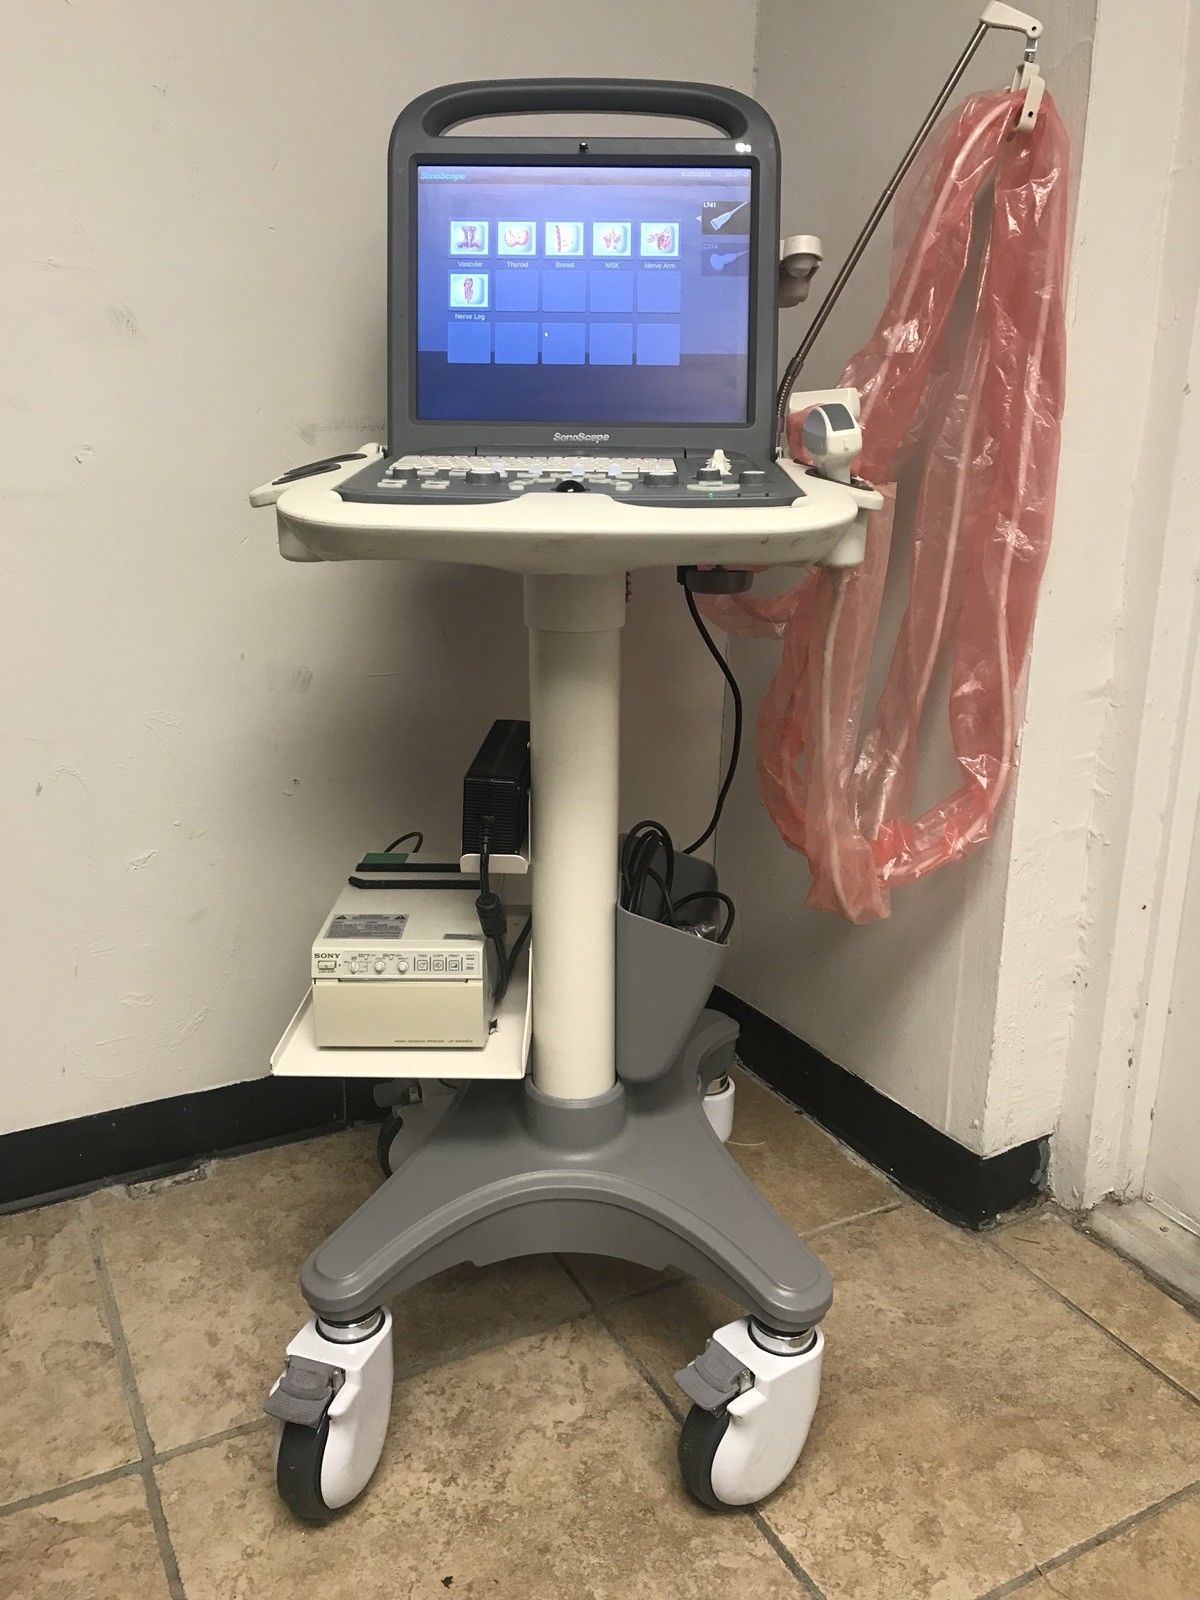

DIAGNOSTIC ULTRASOUND MACHINES FOR SALE

2017 GE ML6-15 -RS for GE S8 ,S6 Ultrasound

Sale price$ 7,675.18